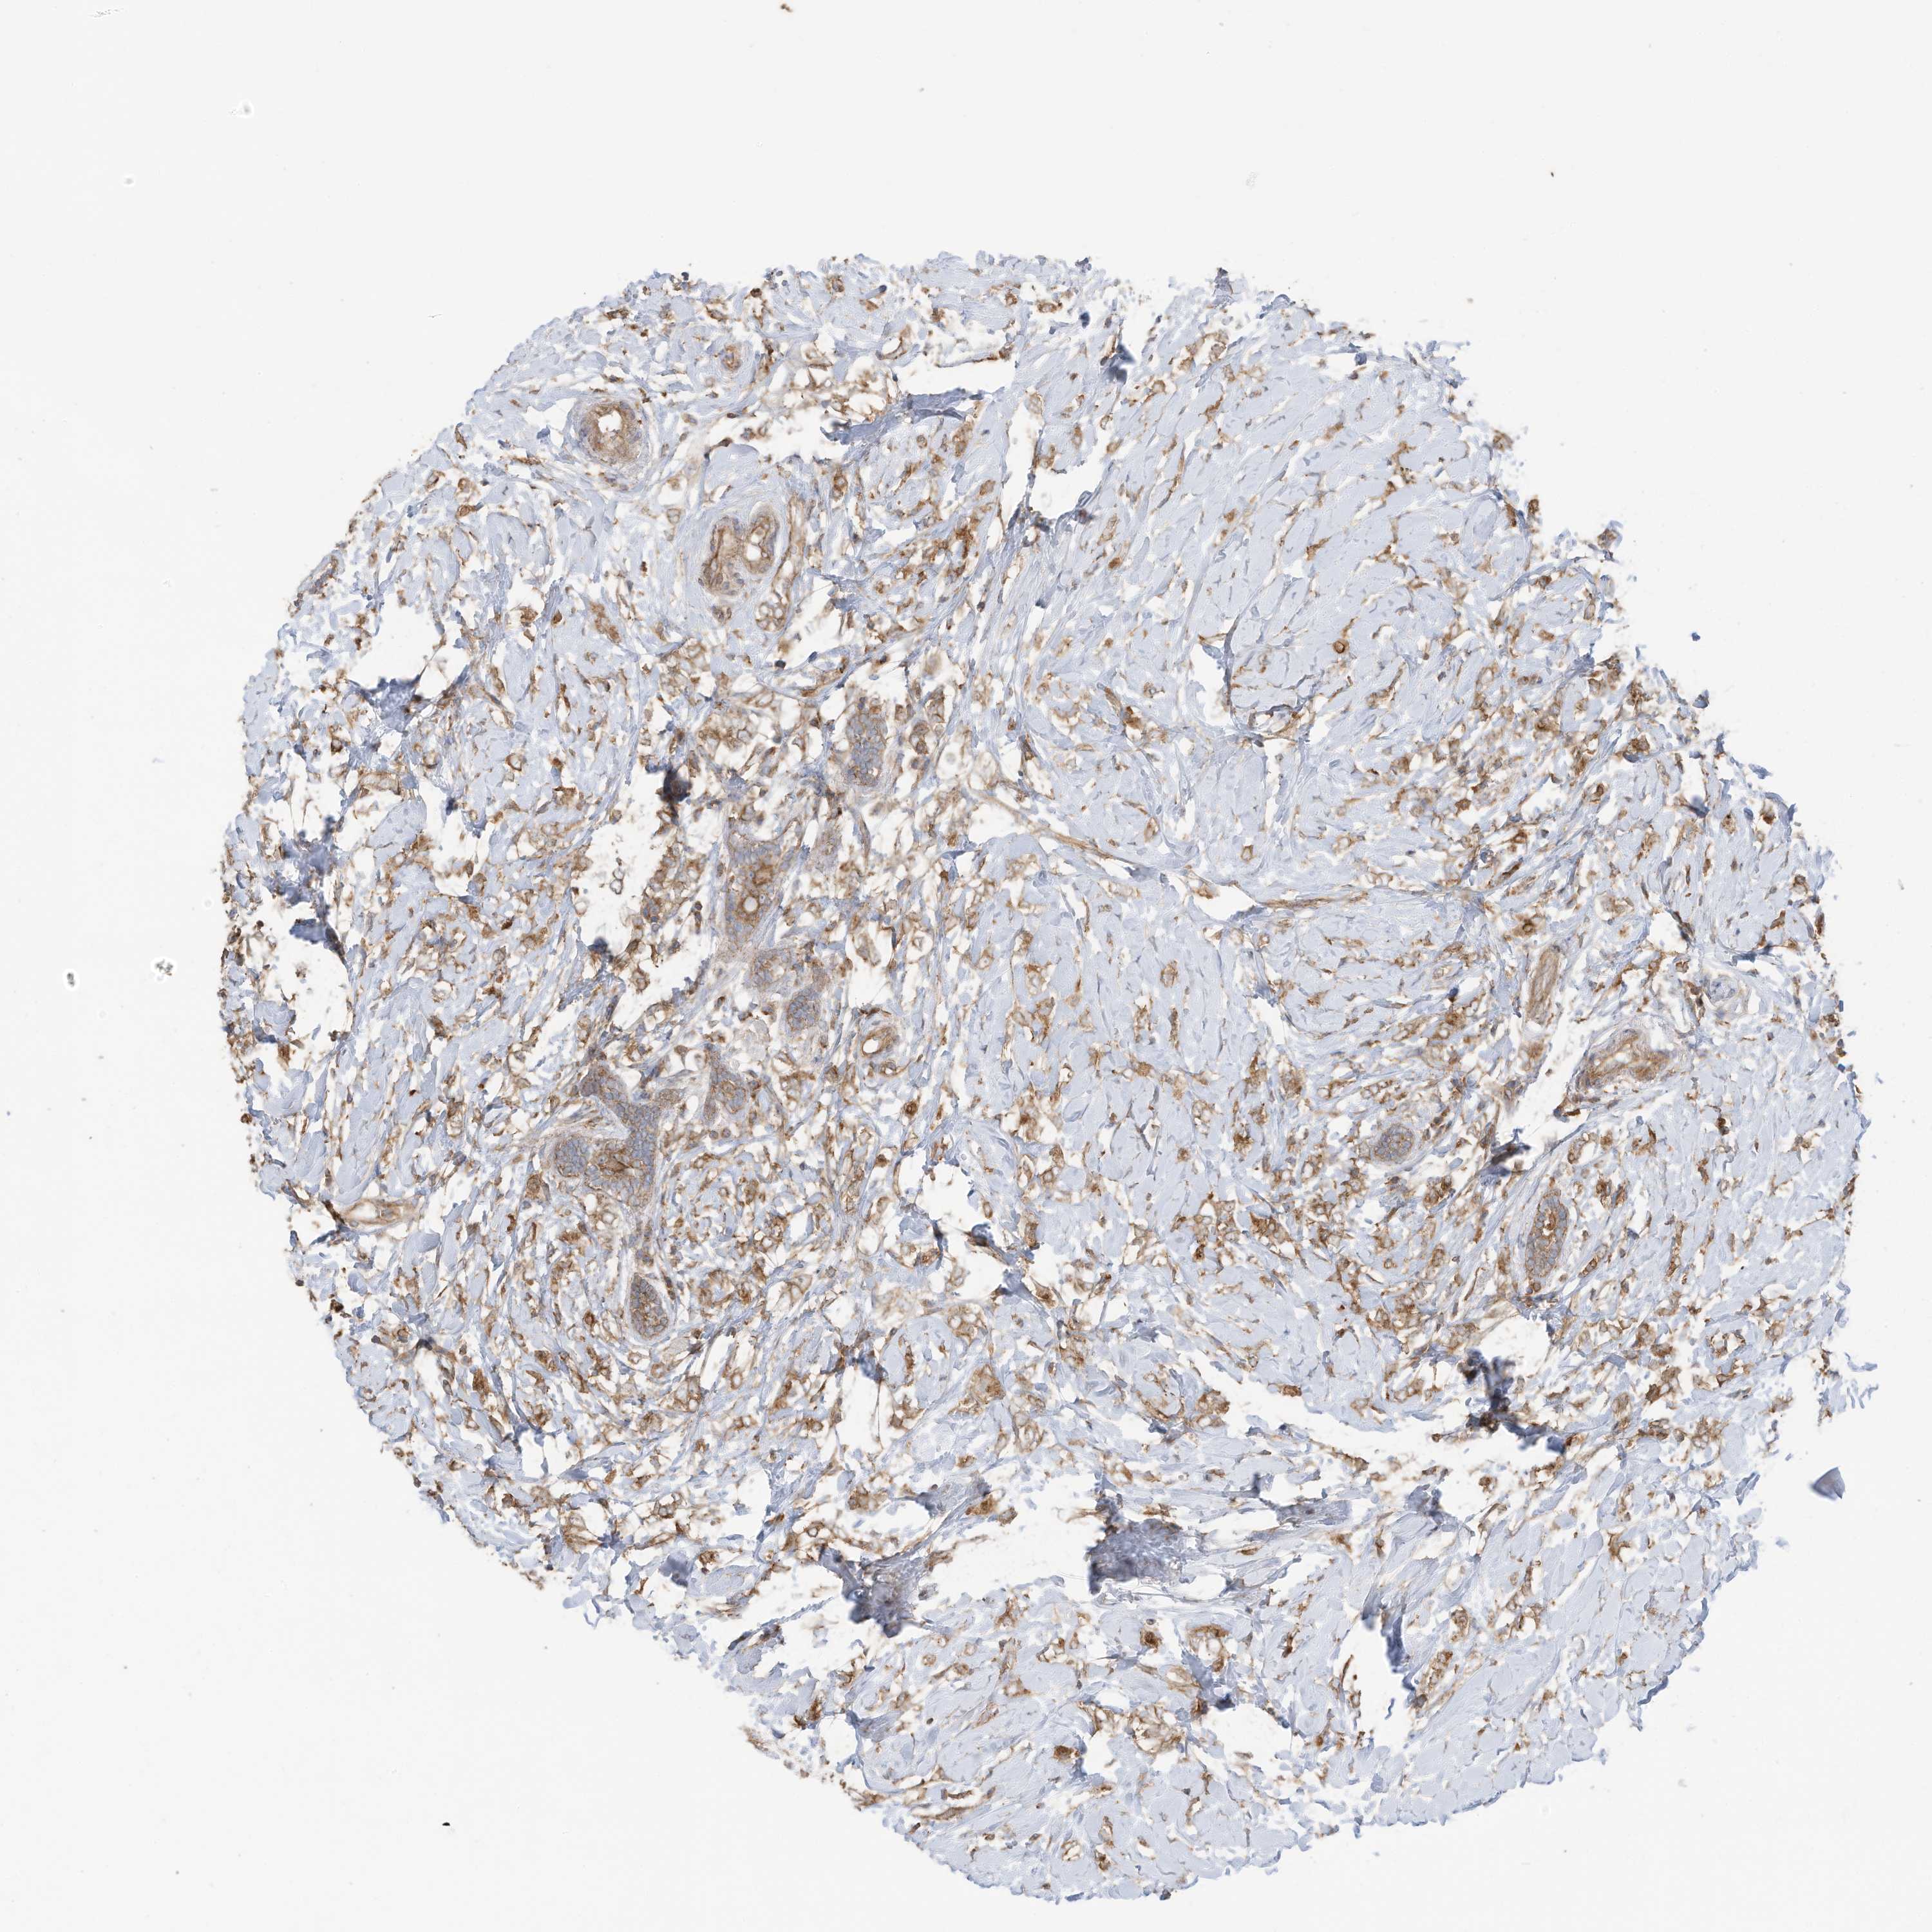

CANCER BREAST CANCER Show tissue menu

BRCA TCGA BRCA VALIDATION PROTEIN EXPRESSION